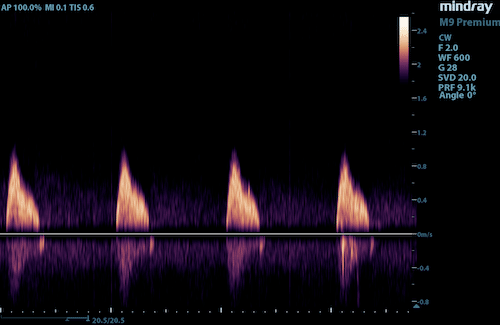

Continuous Wave (CW)/Pencil Ultrasound Transducers

A Continuous Wave (CW) transducer has a circular-shaped tip. These non-imaging transducers are dedicated to Doppler interrogation to help clinicians see waveforms and hear blood flow. CW transducers are used for vascular, cardiac, and transcranial applications.

TEE transducer

Heart visualized with TEE transducer